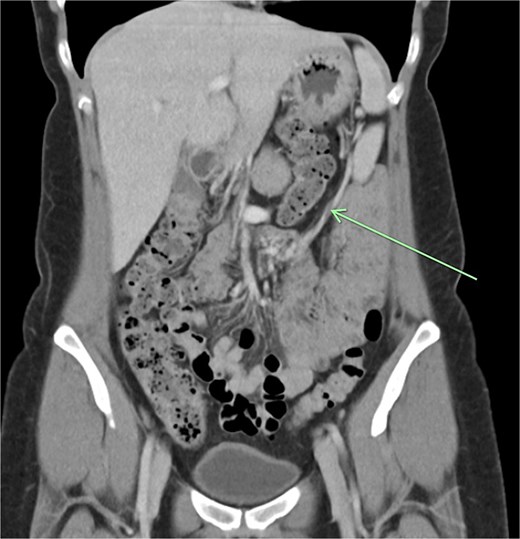

Transvaginal ultrasound demonstrated a large solid vascular mass in the left adnexa measuring 50 × 52 × 54 mm separate to the left ovary. Sonographic appearances of the uterus, endometrium, ovaries, kidneys, and bladder were reported as normal. Computed tomography (CT) demonstrated a solid rounded lesion with moderate enhancement measuring up to 55 mm. This lesion was reported as most likely to represent a broad ligament or pedunculated fibroid.

The aforementioned CT was reassessed intraoperatively together with this new information. The vascular pedicle was traced from the lesion towards the splenic vessels at the tail of the pancreas. A normal spleen was identified in the left upper quadrant (Figs 3–5). The overall impression was that this lesion represented accessory splenic tissue. The general surgery team called the patient’s next of kin, who gave consent to proceed with an excision of this wandering accessory spleen.

Long vascular pedicle leading to accessory spleen in the pelvis.